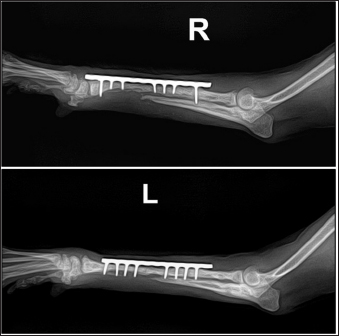

A two-step surgical plan was developed for managing the fractures. The remaining pin was removed in the first surgery and a CEF was applied for temporary fixation (Fig. 2A and B). Pins used included two 0.9 mm K-wires placed proximally and distally in a crossed manner, and one 1.2 mm olive wire placed in a single location. Anticipation of bone regeneration around areas of bone lysis near screw holes, and physical rehabilitation focused on inducing forelimb use until the second surgery. During the 6-week maintenance period of the temporary external fixation device, partial bone regeneration was observed in some areas of bone loss (Fig. 2C and D). Although forelimb ambulation remained plantigrade, there was an improvement in utilizing the limb smoothly with weight-bearing. In the second surgery, the CEF device was removed, and a surgical approach was made to apply the bone plate. The atrophied fracture sites on both sides showed no signs of bone regeneration and were partially debrided to expose the bone marrow cavities. The fracture was then fixed with a long bone plate and 1.5 mm screws. Autografts were harvested from the iliac wing and transplanted around the fracture site. This procedure was performed identically on both limbs with the fascia and skin closed in a standard manner. Additionally, CEF methods involved applying 0.9 mm K-wires, the same size as those used in the first surgery, above and below the plate on the fractured radius to provide further stability (Fig. 3).

Fig. 2. Radiographs taken immediately after the first surgery and 6 weeks postoperatively, showing the effects of temporary circular external fixation on bone remodeling. (A) Immediate postoperative view of right radius and ulna. (B) Immediate postoperative view of left radius and ulna. (C) 6-week postoperative view of right radius and ulna. (D) 6-week postoperative view of left radius and ulna.